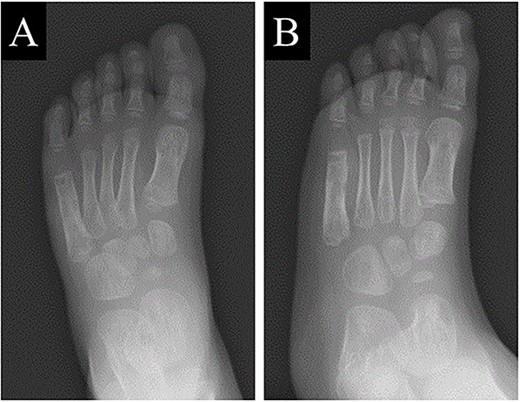

A 21-month-old Japanese female infant presented with a swollen mass on the dorsolateral aspect of the left foot. Her parents noticed the mass and brought the patient to our hospital. The patient had no past medical histories or complications prior to the occurrence. In addition, she received the BCG vaccine at the age of 4 months in Japan. At first visit to our hospital, physical examination revealed the ~3 × 3 cm mass was located on the dorsolateral aspect of the left foot and was hard accompanied by local heat (Fig. 1). Plain radiographs of the left foot showed a lytic lesion without periosteal reaction in the fifth metatarsal bone (Fig. 2). Magnetic resonance imaging (MRI) showed an isointense lesion on T1-weighted images and a hyperintense lesion on T2-weighted images around and within fifth metatarsal (Fig. 3). Gallium scintigraphy revealed intense uptake in the patient’s left foot (Fig. 4). In addition, laboratory examination was within normal. Based on medical history, clinical and imaging findings, we considered the possibility of neoplasia or osteomyelitis and performed an open debridement and biopsy of the lesion to make a diagnosis. The lesion was yellow and consisted of weak, adipose-like tissue that surrounded and continued into the inferior of the fifth metatarsal bone (Fig. 5). The lesion inside and outside the bone was resected as much as possible. Histopathologic examination of the lesion showed granulomatous inflammation including anaplastic giant cells, Langerhans-type giant cells and caseous necrosis (Fig. 6). Based on these results, TB or BCG osteomyelitis was considered as a diagnosis. The tuberculin test was positive, but the QuantiFERON TB test was negative. In addition, samples analyzed using polymerase chain reaction did not identify M. tuberculosis, but did identify the BCG Tokyo-172 strain. Per these findings, the patient was diagnosed with BCG osteomyelitis of the fifth metatarsal and oral treatment with anti-TB medicine including isoniazid (100 mg/day) and rifampicin (150 mg/day) was started. Clinical findings included reduction in swelling of the mass and gradual remodeling of the lytic lesion of the fifth metatarsal on plain radiographs (Fig. 7). However, 10 months after starting the anti-TB treatment, the mass recurred, and MRI revealed a residual high-intensity lesion around and inside the fifth metatarsal on T2-weighted fat-suppressed images (Fig. 8). It was determined that the lesion was difficult to control with anti-TB treatment alone, so an open debridement for the lesion was performed again. Histopathologic examination of the lesion revealed an epithelioid granuloma with necrosis. Therefore, the anti-TB treatment was continued. Six months after the second surgery, clinical and radiographic image findings showed complete improvement (Fig. 9). As a result, anti-TB treatment was ended. At the time of writing this report, 8 years after starting anti-TB treatment, there has been no recurrence.

Plain radiographs of the left foot showed the lytic lesion of the fifth metatarsal was remodeled gradually in (A) anteroposterior and (B) oblique views.